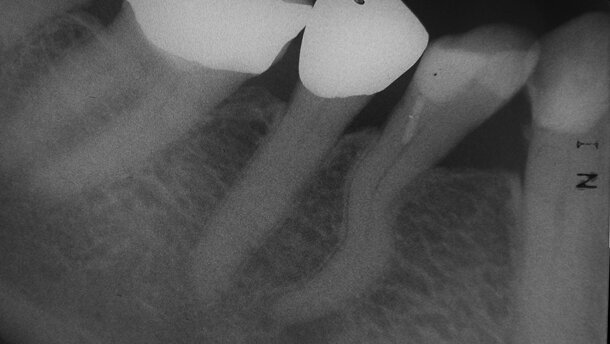

_Une patiente âgée de 81 ans s’est présentée avec une douleur typiquement causée par une pulpite dans le secteur mandibulaire droit. Les résultats du test de sensibilité étaient positifs et durables pour la 2e prémolaire inférieure droite (n° 45) et négatifs pour la 1re prémolaire inférieure droite (n° 44). Ceux du test de percussion étaient contradictoires, négatifs pour la dent 45 et légèrement positifs pour la dent 44. Une radiographie révélait une lésion apicale d’origine endodontique dans la dent 44 et aucun signe diagnostique dans la dent 45.

Au vu de sa dimension, la lésion endodontique de la dent 44 devait probablement être présente depuis plusieurs mois. Pourtant, la cause de la douleur aiguë siégeait dans la dent 45. La radiographie montrait en outre une morphologie radiculaire en S de la dent 44 qui laissait présager un traitement endodontique, non simplement difficile, mais relevant d’un véritable défi majeur.

Après un nettoyage et une mise en forme réalisés manuellement avec des limes de Hedström, suivis par une nouvelle irrigation et une préparation accomplie au moyen de mouvements alternatifs, une radiographie a été prise pour vérifier la longueur du canal radiculaire.